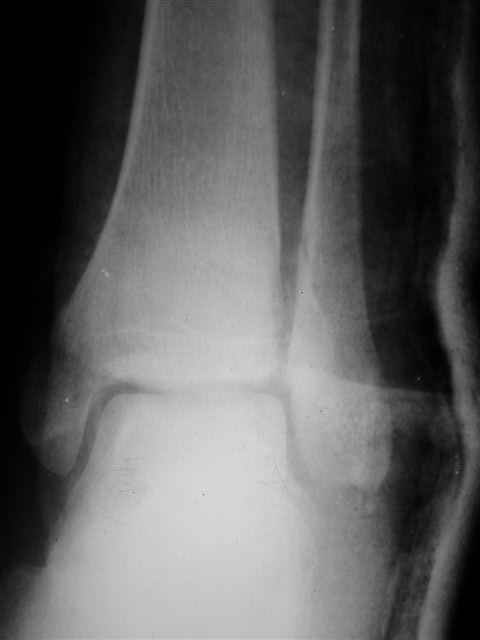

> Если Вас не затруднит, пришлите, пожалуйста, рентгенограммы. Я

> интересуюсь тактикой лечения повреждений голеностопного сустава.

> Хочется посмотреть, как лечат коллеги.

Ничего сверхъестественного, но если есть интерес, то в понедельник пересниму Рг-граммы и отправлю.

Я предупреждал, что ничего сверхъестественного. Каюсь, что одна из спиц прошла несколько дальше, чем нужно было, но главное - перелом стабилизирован и больной работает суставом в полном объёме, несмотря на представленную раннее травму коленного сустава.